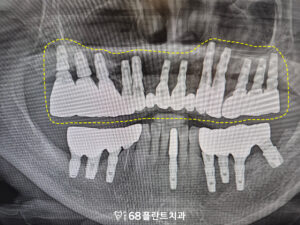

먼저 치아를 발치한 후

오른쪽 위는 상악동거상술을 진행하며

상악동 내부에 뼈가 부족한 부분을

보충하기 위해 뼈 이식을 실시했습니다.

이후, 충분히 시간이 지난 후,

임플란트 식립을 진행하여

보다 견고한 결과를

얻을 수 있도록 했습니다.

롱브릿지 부분도 임플란트를 식립하여

기존의 브릿지가 받던 하중을

분산시킬 수 있도록 했습니다.

이렇게 식립 후 치유 기간을 기다린 뒤

염증 없이 잘 치유되어

보철 작업을 진행한 후

마무리하였습니다.